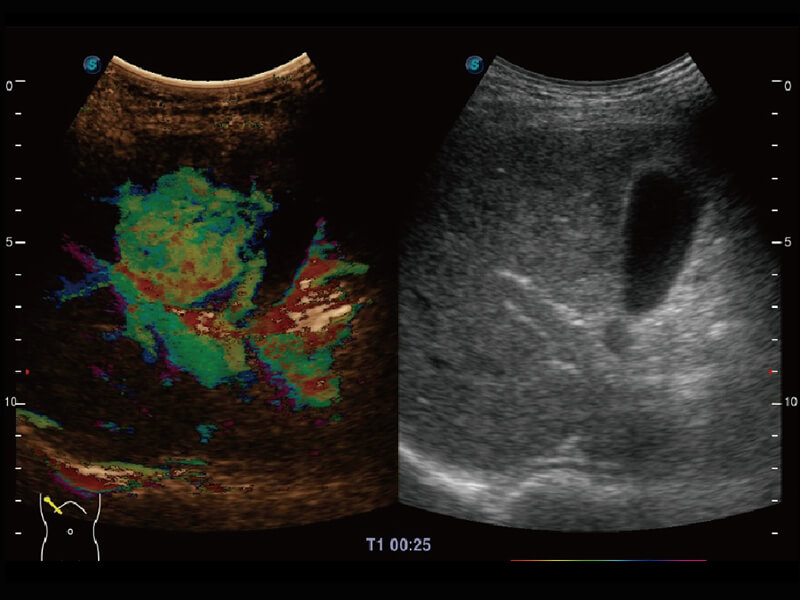

S60探头工艺,从前端信号处理每一个环节采集无损声学数据,真实还原组织原貌,再现解剖细节。

超宽频带技术,为容积成像带来优质的二维图像基础,为您呈现丰富的结构细节,栩栩如生地展示宝宝的宫内形态以及各种组织的立体结构。